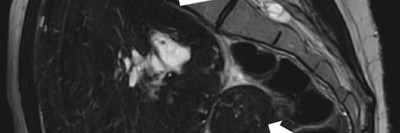

Ein Abstrich vom Gebärmutterhals wird auf ein Objektivträger geschmiert/© Tatiana Buzmakova / Getty Images / iStock (Symbolbild mit Fotomodellen), MRT des Beckens: Uterus und Ovarialtumoren/© Hosten AK et al. / all rights reserved Springer Medizin Verlag GmbH, Ultraschall eines Adnextumors/© Markus Hoopmann, Mehrere Personen erhalten Chemotherapie/© FatCamera / Getty Images / iStock (Symbolbild mit Fotomodellen), Subtypen des epithelialen Ovarialkarzinoms/© Springer Medizin, Frau mit Kopftuch und Infusion/© FatCamera / Getty Images / iStock (Symbolbild mit Fotomodell), Gewinner des Galenus-von-Pergamon-Preises 2025 in der Kategorie Specialist Care/© Marc-Steffen Unger, Frau bereitet einen Smoothie zu/© Tijana Simic / Getty Images / iStock (Symbolbild mit Fotomodell), Subkutane Injektion/© myskin / stock.adobe.com (Symbolbild mit Fotomodel), Eine ältere Frau bekommt eine intravenöse Therapie/© peopleimages.com / stock.adobe.com, Ärztin betrachtet Mammografie-Befund/© Gorodenkoff / stock.adobe.com (Symbolbild mit Fotomodellen), Frau bei Mammografie-Untersuchung/© Myroslava / Stock.adobe.com (Symbolbild mit Fotomodellen), Frau setzt sich ein Pflaster auf den Schenkel/© svetikd / Getty Images / iStock (Symbolbild mit Fotomodell), Lungenmetastasendiagnostik/© Krämer S. et al. / all rights reserved Springer Medizin Verlag GmbH, Verlagerung von Oberbauchorganen in den Thorax/© Koop H (Mit freundl. Genehmigung der Radiologischen Abteilung), Multiple Papeln auf der Hand bei chronischer Prurigo/© E. Steffens et al. doi.org/10.1007/s00105-023-05131-8 unter CC-BY 4.0, Hysterektomie/© nkeskin / Getty Images / iStock, Search Icon, Person setzt DNS-Probe in Maschine ein/© Vit Kovalcik / stock.adobe.com, Mann raucht Joint/© Daniel Sierralta / Westend61 / stock.adobe.com (Symbolbild mit Fotomodell), Blut in Toilette/© stylefoto24 / stock.adobe.com